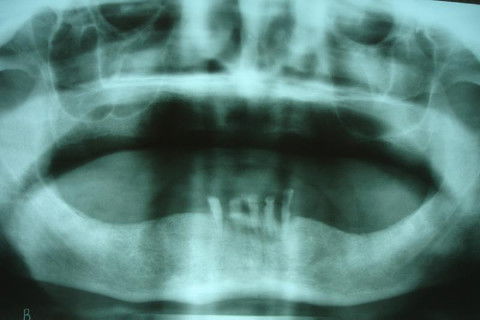

RX Panorâmico para exodontias e instalação de implantes imediatos na região entre os forames mentuais.

Paciente sexo masculino, 89 anos, portador de prótese total superior, restos radiculares inferiores e perda de dimensão vertical. O plano de tratamento proposto foi de restabelecer a DV do paciente confeccionando prótese total superior e overdenture inferior com carga imediata sobre 2 implantes com abutment e attachment magnético.